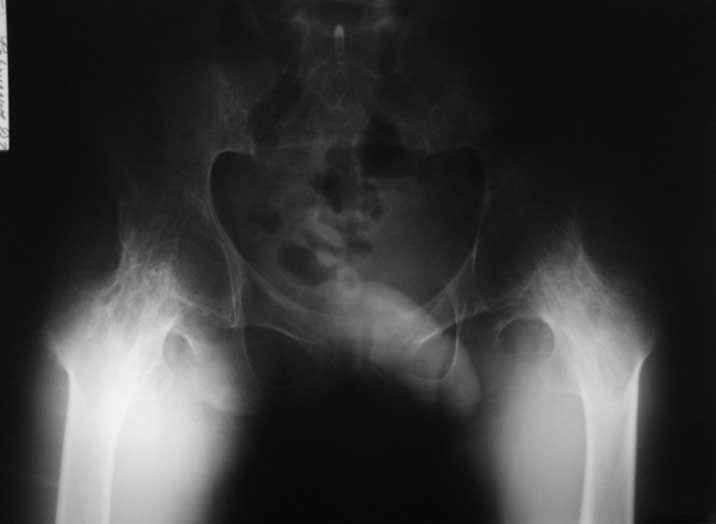

Уважаемые коллеги. пациент, страдает ревматоидным артритом с детства, ранее докладывался...

костный анкилоз т/б суставов. 4 месяца назад THR левого т/б сустава, движения в т/б суставе приличные - с/р 90/5/0, движения в коленном суставе ухудшились - с/р 120/45/0. В настоящее время конечность неопорна из-за сгибательной кнтрактуры в к/с Вопросы о дальнейшей тактике лечения (пациенту 28 лет):1. рассматриваются варианты остеотомий (бедра, б/б кости), насколько это целесообразно, учитывая необходимость артротомии (остеофиты), каков может быть ожидаемый результат? варианты остеотомий (бедро или голень)?2. эндопротезирование к/с: мягкотканный дисбаланс- достаточно будет релиза капсулы и связок или мышцы тоже (учитывая разгибание в т/б после эндопротезирования и натяжение мышц на уровне колена после этого) Чего опасаться и к чему быть готовым?3. другие варианты? ссылки на литературу?собств наблюдения?С уважением Максим Агалаков